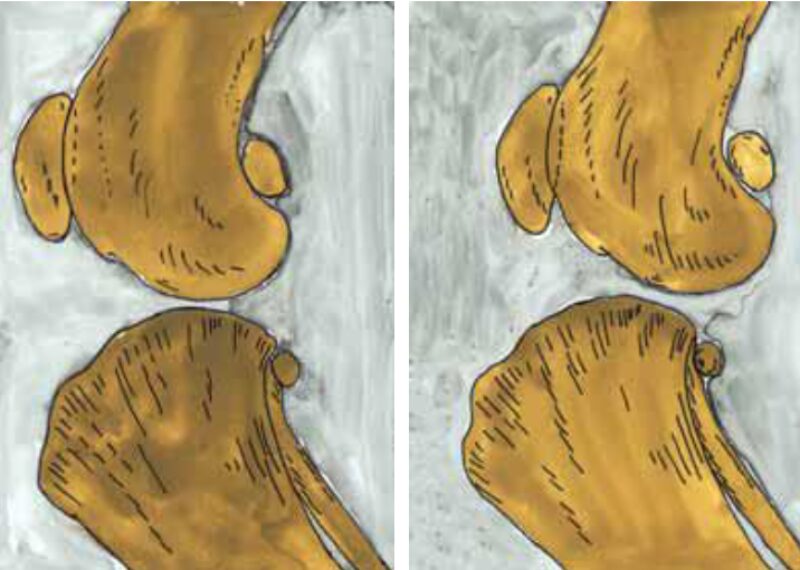

Eine wichtige Differenzialdiagnose ist die generalisierte Bandlaxizität im Rahmen einer Bindegewebsschwäche. Hier entsteht die Schublade durch Überdehnung der Bandstrukturen, nicht durch eine Ruptur. Typisch sind eine häufig beidseits auslösbare Schublade, fehlende Schmerzhaftigkeit, kein Gelenkerguss und eine weitgehend normale Belastung. Auffällig ist oft die Laxizität mehrerer Gelenke. Der Tibia-Kompressionstest ist meist negativ, die Reflexe unauffällig. Bildgebend zeigt sich häufig ein gleichmäßiger Gelenkspalt ohne entzündliche Begleitzeichen. Therapeutisch stehen Muskelaufbau, Koordinations- und Propriozeptionstraining sowie Verlaufskontrollen im Vordergrund. Unbehandelt kann eine ausgeprägte Bandlaxizität langfristig sekundär zu Gelenkschäden bis hin zum Kreuzbandriss führen.